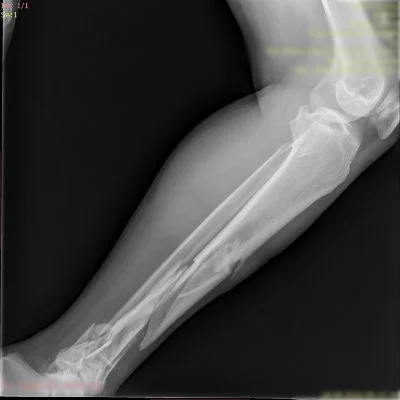

Görüntüleri büyütmek için resmin üstüne tıklayınız.